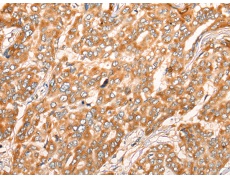

IHC positive control: |

Human liver cancer and Human thyroid cancer |